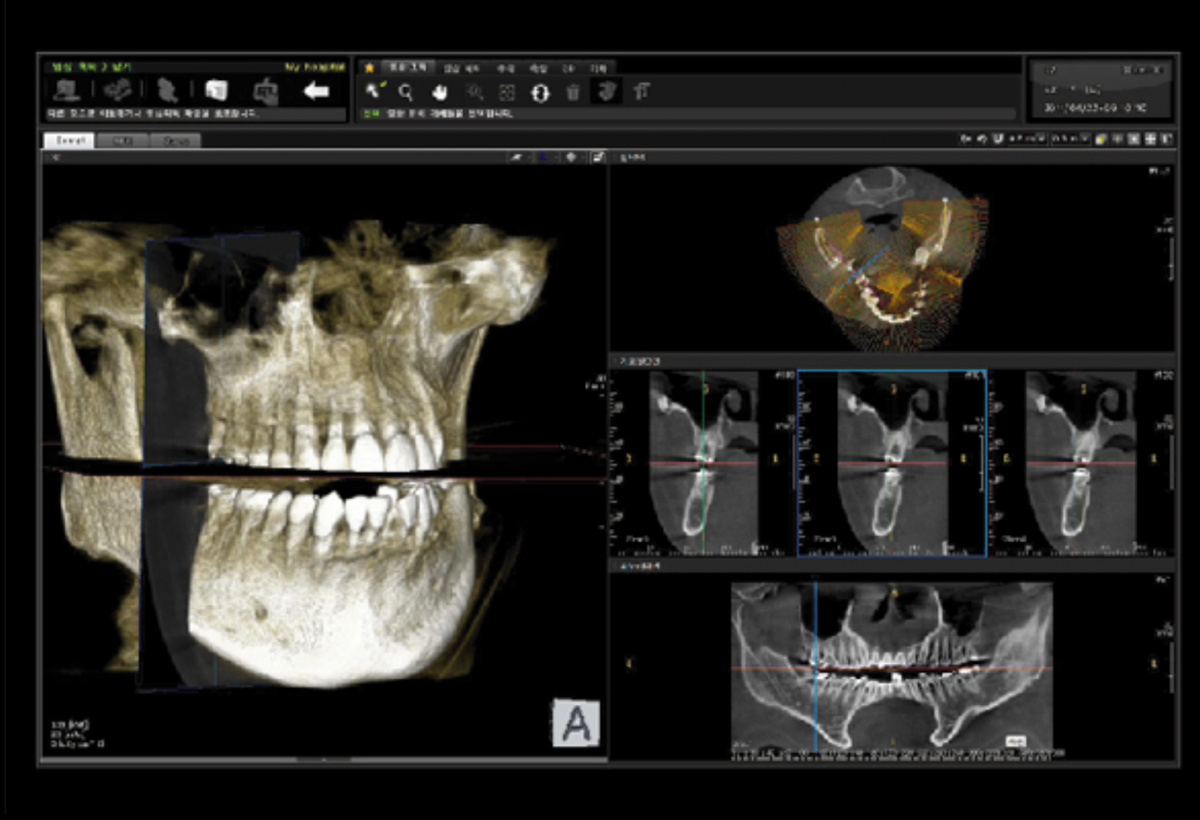

Немаловажным, а может главным вопросом, является универсальность программы-просмотровщика, в которой будут работать врачи-стоматологи. У Papaya 3D есть два варианта программ: Triana и OnDemand3D. Оба просмотровщика обладают схожим интерфейсом и имеют самые важные опции, а именно:

• режим MPR (многоплоскостная реконструкция). Именно здесь выстраивается интересующий участок челюсти или зуба для анализа.

• панорамный реформат. Возможность постройки классической и сегментарной панорамы позволяет продемонстрировать план лечения пациенту, а также оценить расположение анатомических структур на боковых кросс-секциях.

• модуль дентальной имплантации. Возможность виртуальной установки дентального имплантата с анализом окружающей костной ткани. В библиотеке представлен широкий спектр имплантологических систем с индивидуальной прорисовкой имплантата.

• выделение нижнечелюстного канала позволяет продемонстрировать расположение важного анатомического образования и определить зону безопасности при проведении лечения.

• функции плотности, линейных измерений и угла – необходимы для получения полноценной информации для последующего лечения.

• 3D режим – показывает трехмерную модель челюсти с целью определения аномалий, деформация, а также визуализации виртуальных имплантатов.